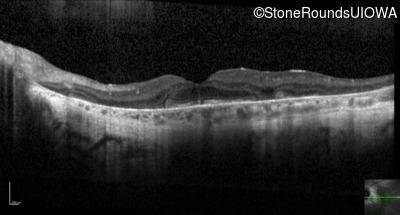

Optical Coherence Tomography - Right - 20/50 sc

Exemplar / OCT Stack

OCT Stack